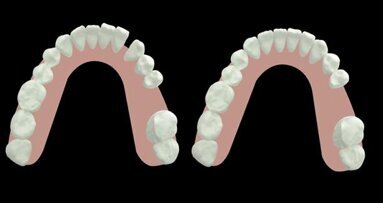

The treatment plan was developed using a fully digital workflow. The DICOM files obtained from the preoperative CBCT scan were used to generate a 3D reconstruction of the maxilla, which allowed for the virtual design of the ideal bone volume for the placement of three implants in sites #15, 16 and 17 (Figs. 6a-d; 7a & b). Subsequently, the customised mesh corresponding to the increased volume in the patient’s maxilla was created virtually (Figs. 8a-f).